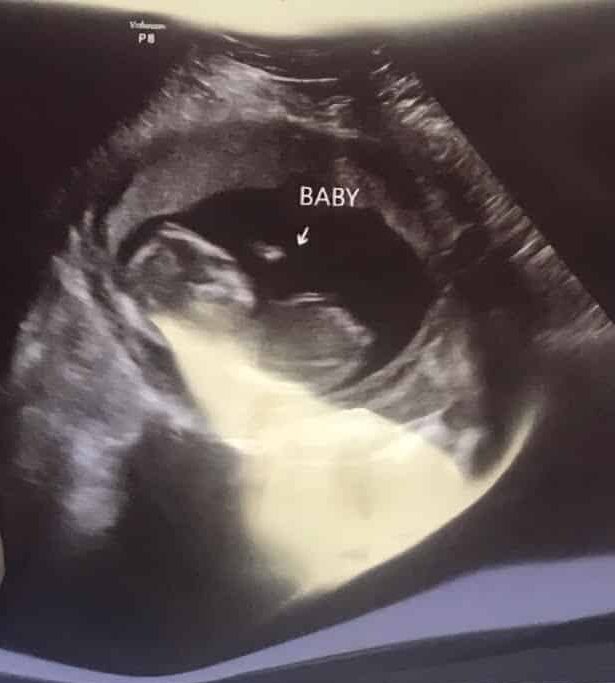

Baby Girl

Domestic Adoption | United States

We started the process of adoption in March 2025. We expected it would take a year or more to be matched with a Birth Mom. Much to our great surprise and delight, we were matched after only 1 month! Our Birth Momma is wonderful! She does have other children and she is working very hard to provide for them. Due to a series of events she found herself pregnant and selected adoption as a loving choice for this Baby. She is due to deliver the Baby Girl (whom we plan to name Ariella Mercy) on December 7, 2025. Birth Momma currently lives in Mississippi. So, we will plan to go down and be with her when Baby Girl is born. We will be required to stay in Mississippi for about 7-10 business days and then will joyfully bring her home!